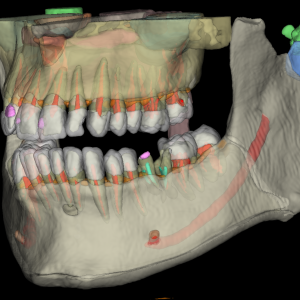

- 3D snimanje zuba: CBCT snimak – trodimenzionalni prikaz kosti, korenova i sinusa – neophodan za implantologiju i hirurgiju.

Posebna pogodnost – upotreba veštačke inteligencije za obradu snimka: Napredna 3D obrada – AI prepoznaje i obeležava čak do 135 anatomskih struktura, takodje, naše ortodontske analize podržane su veštačkom inteligencijom (AI), što omogućava izradu preciznih parametara za svega nekoliko minuta.

Precizni hirurški zahvati: Softver pomaže u planiranju operacija tako što po potrebi izdvaja (izoluje) specifične strukture (npr. nerve ili sinuse), omogućavajući hirurgu da unapred vidi svaki detalj operativnog polja.

Napredna 3D obrada: AI koristimo i za procesiranje 3D snimaka, gde sistem automatski prepoznaje i obeležava čak 135 anatomskih struktura, pružajući stomatologu neverovatan nivo detalja.

Planiranje implantata: Tehnologija nam omogućava simulaciju položaja buduće krunice direktno na snimku, što osigurava idealno pozicioniranje implantata u odnosu na zagrižaj.